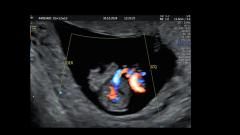

@diagnóstico 95